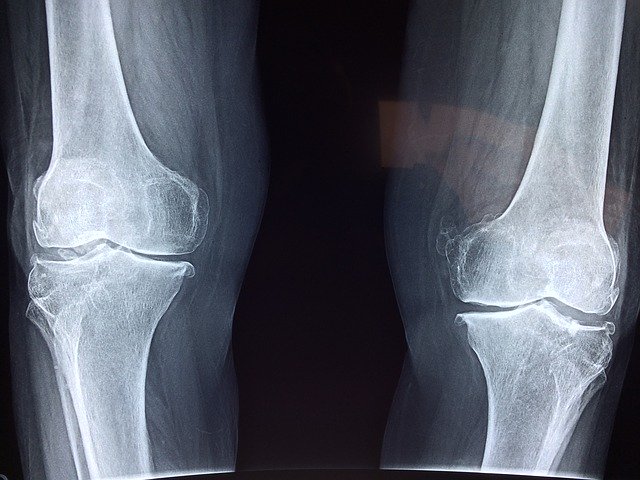

Although some knee (patella) damage can take weeks or months to become noticeable, you must always obtain immediate diagnostic care and treatment when swelling and pain are present. The information below reviews basic facts about the structure of the knee (or patella), how common knee injuries occur, frequent symptoms and preferred approaches to treatment.

• Due to the many bones, cartilage, and ligaments that support it, the knee is the largest joint located in the human body.

• The three bones that join each other to form the knee are the tibia (shinbone), the femur (the thighbone), and the patella (kneecap).